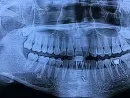

Когда прошло действие обезболивающего укола, появилась боль, что не могла даже говорить. Сегодня 4-ый день после обращения, но боль не утихла (пульсирующая, ноющая), пью "Кеторол". Есть легкая отёчность, но незаметна. Не могу есть без обезболивающих таблеток. Сделали панорамный рентген, но не разбираюсь.

На снимке вижу, что пломбировочный материал, которым Вам запломбировали каналы, вышел за пределы канала, что и является причиной болей.

Так как это временное пломбирование, возможно, этот избыток за пределами корневого канала рассосется.